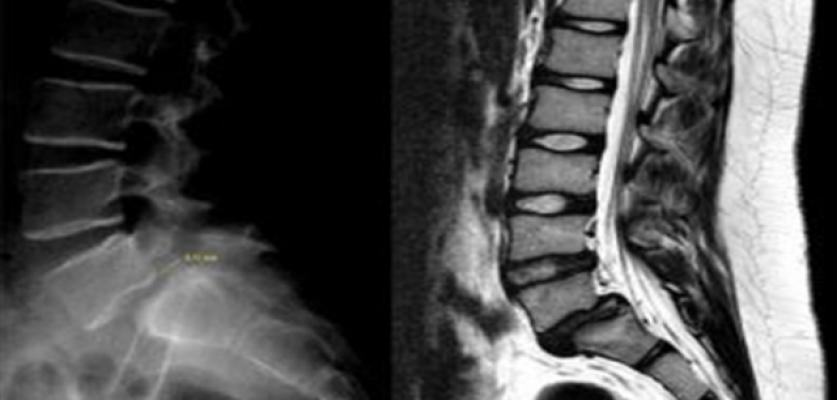

Yüksekten düşme, trafik kazaları gibi yaralanmalarla oluşabilen bel kayması ağrıyla beraber şekil bozukluğuna, bir tarafa doğru eğilmeye ve eğik yürümeye dahi sebep olabilir. Özellikle manuel terapi ile omurga kemiklerini bir tespih dizer gibi yeniden hizalamak mümkündür. Önemli olan nokta, tedaviyi geciktirmemek ve bir fizik tedavi uzmanına başvurmaktır. Sağlık bekletmeye gelmez. Konuyla ilgili daha ayrıntılı bilgi sahibi olmak ve vücudunuza değerlendirme yaptırmak için bizlere ulaşmakta geç kalmayın.